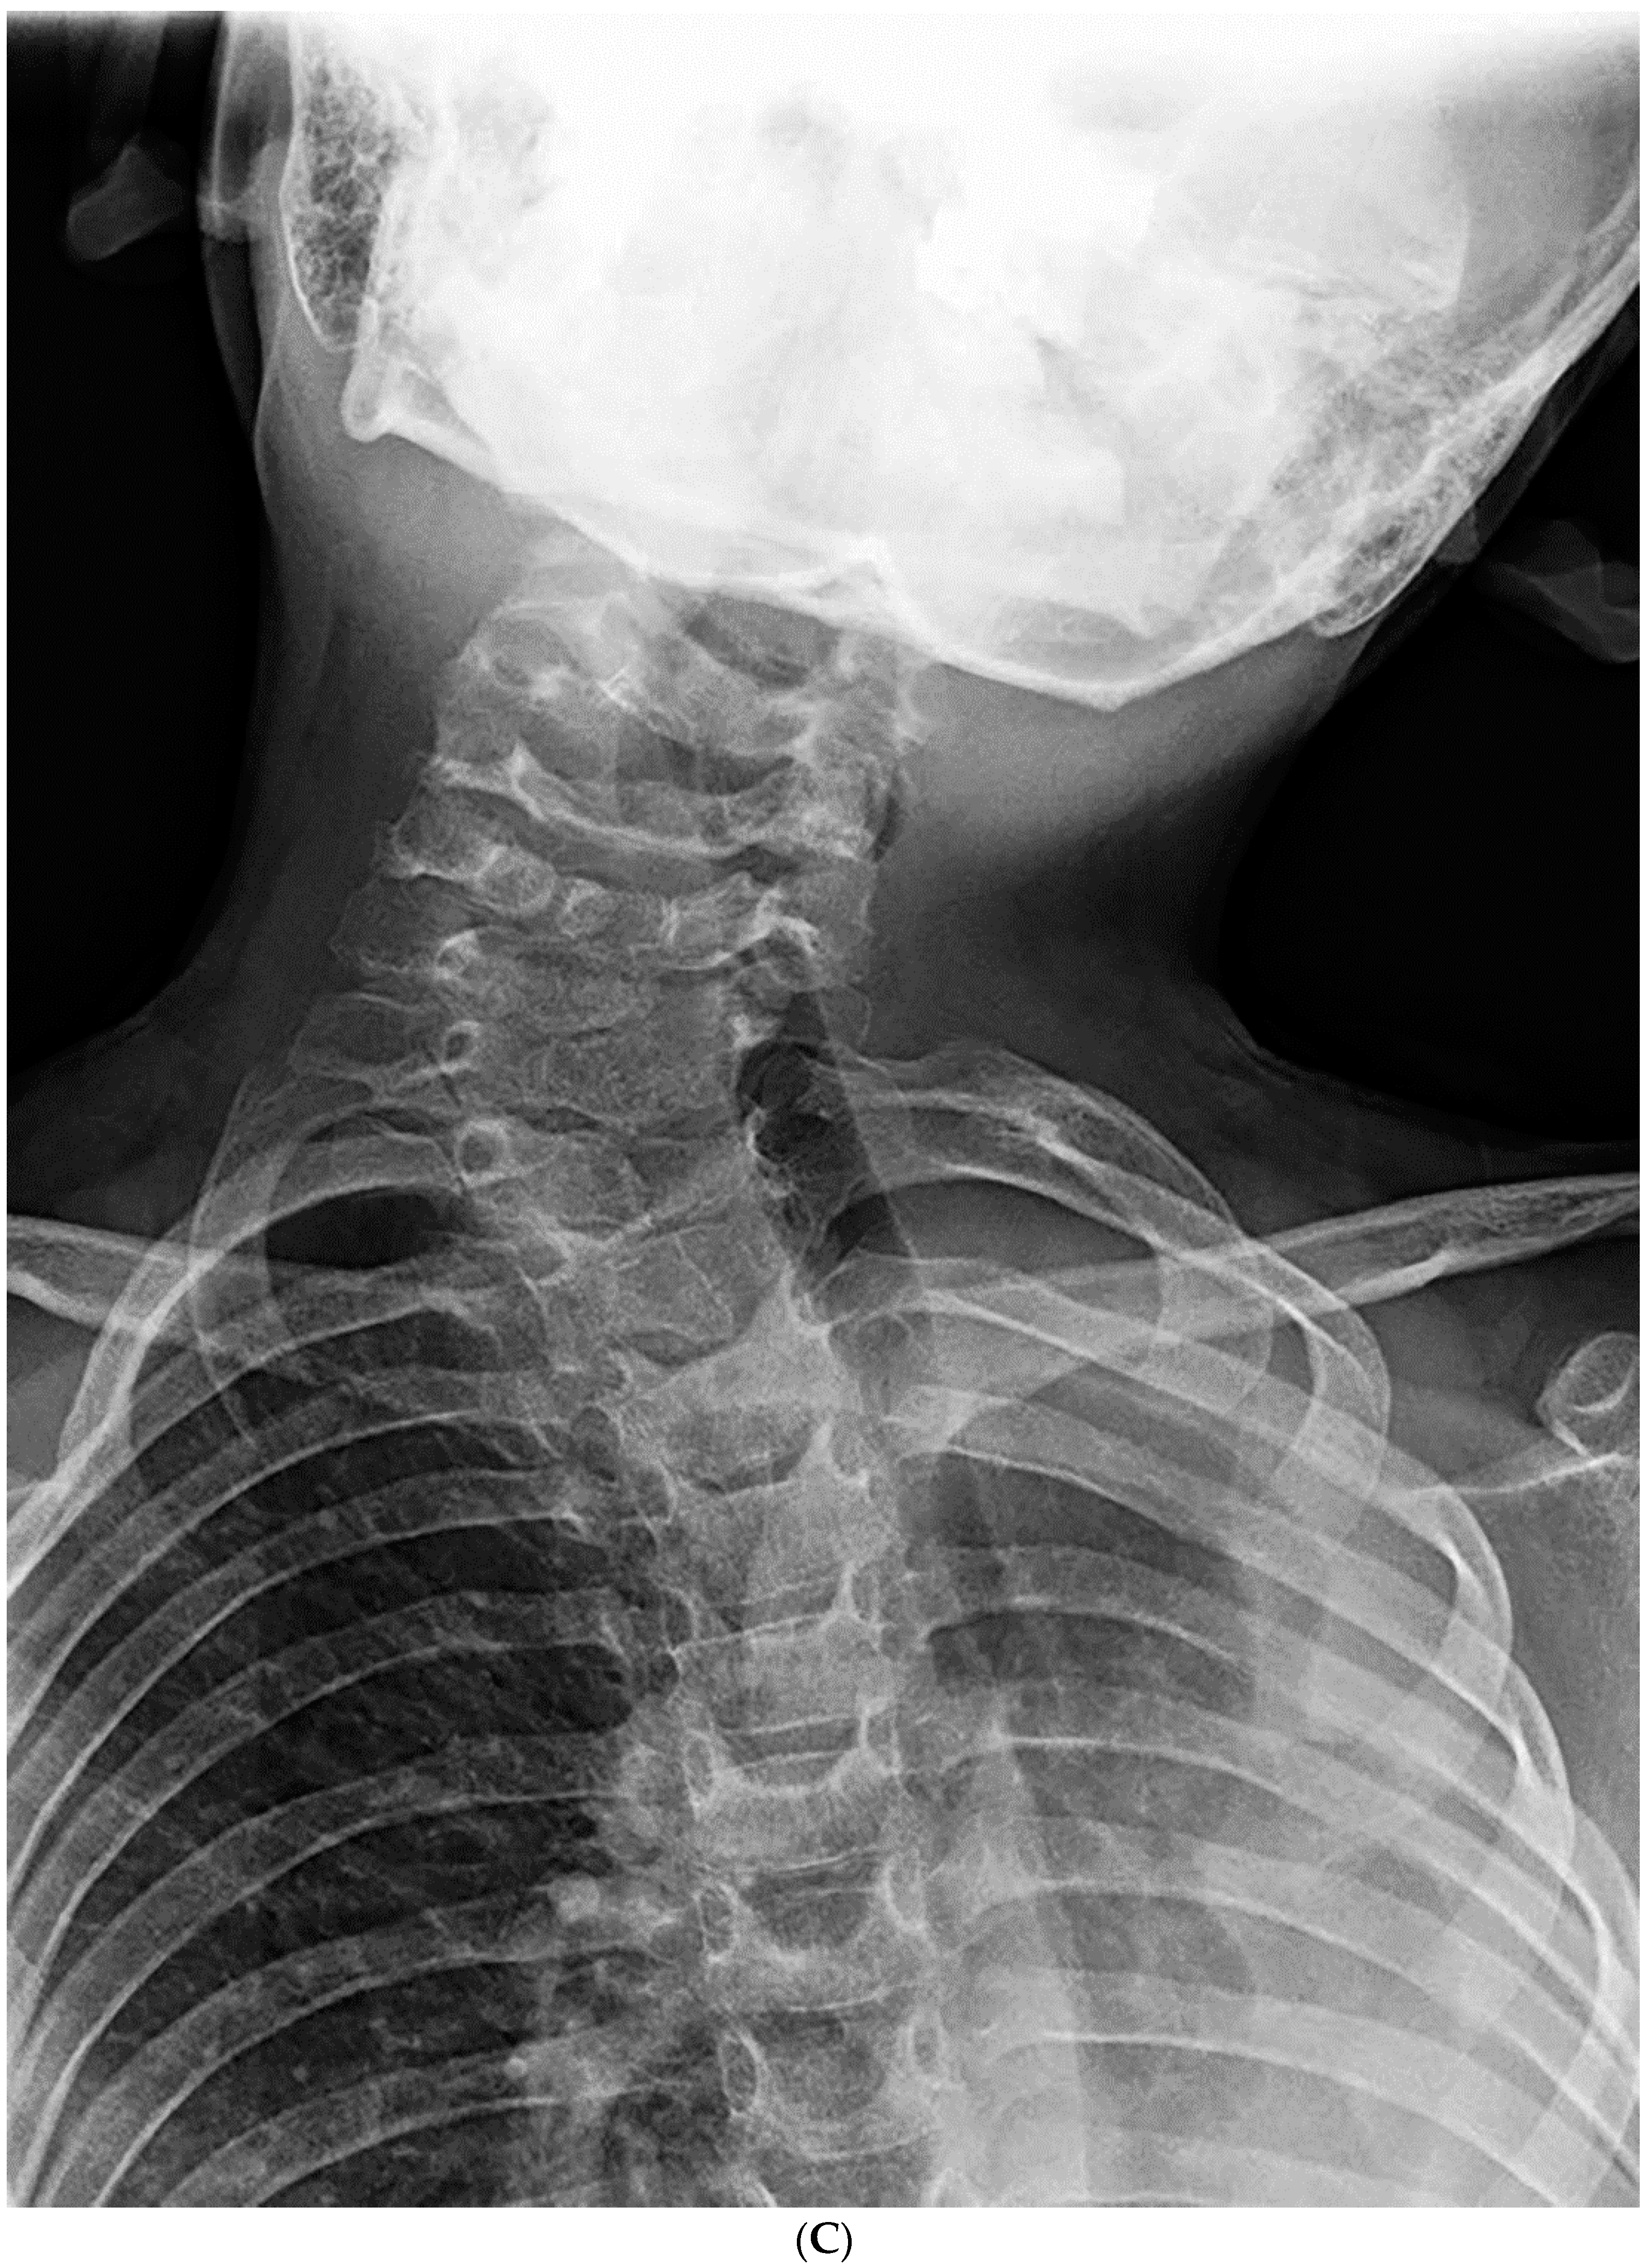

Figure 2.

(A–C). An 8-year-old boy diagnosed with CCS with progression of cervical deformity and compensatory curve. (A) PA radiograph shows a C7 hemivertebra. (B) Lateral radiograph. (C) Coronal CT highlights the left C7 hemivertebra. Patients with thoracic or lumbar vertebral anomalies (such as hemivertebrae, butterfly vertebrae, etc.) were excluded from this study. This was to best ensure that any compensation in the thoracic or lumbar regions was not due to vertebral anomalies in those regions.